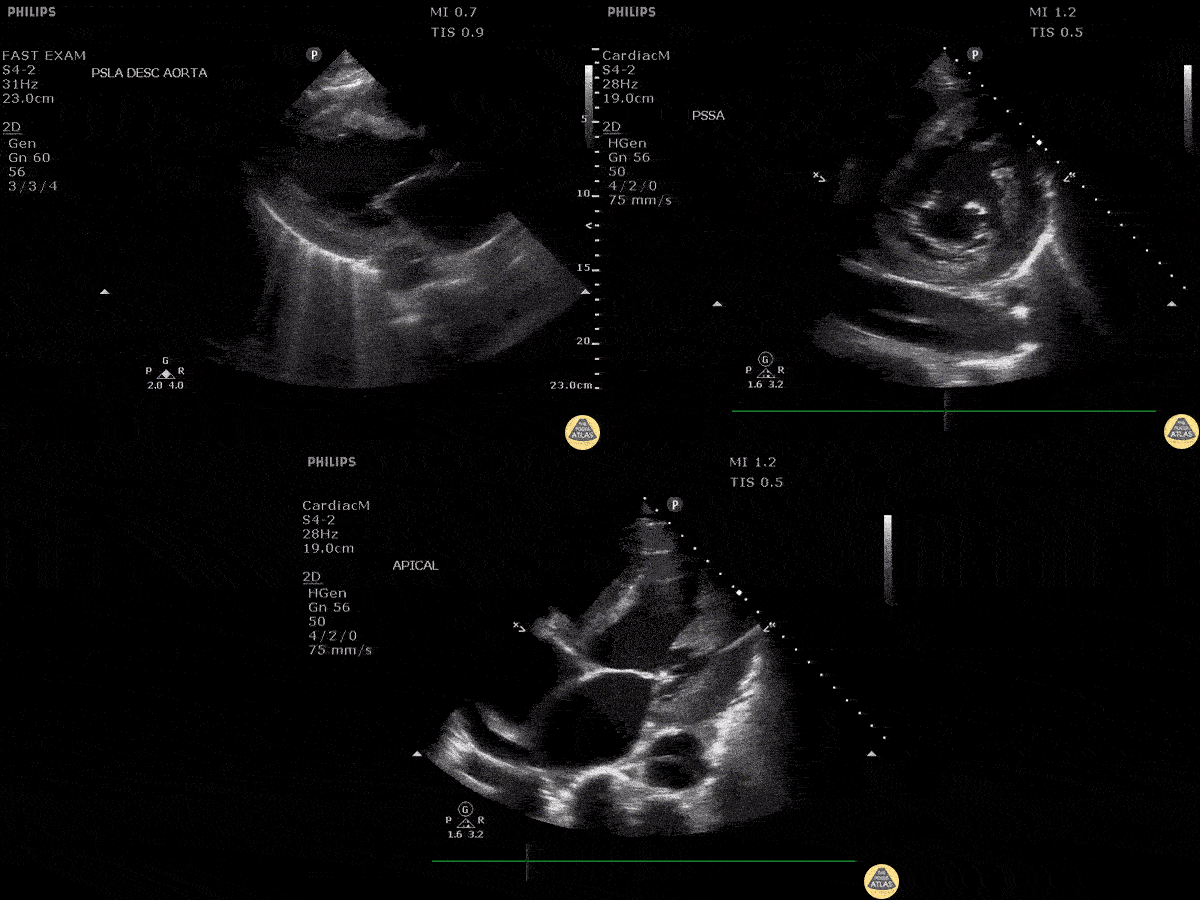

Aorta - Aortic Dissection

A chest pain received an echo and showed evidence of a dissection in the PLAX, PSAX, and AP4C views within the descending aorta. Image courtesy of Robert Jones DO, FACEP @RJonesSonoEM Director, Emergency Ultrasound; MetroHealth Medical Center; Professor, Case Western Reserve Medical School, Cleveland, OH View his original post here